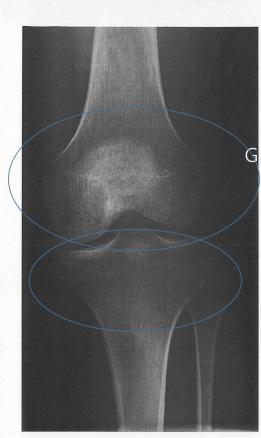

Après deux mois, et malgré la rééducation, une impotence fonctionnelle se manifeste par un flessum à 15 ° du genou gauche, associé à des douleurs. La radiographie révèle des anomalies de la trame osseuse (fig. 1), évocatrices d’un syndrome douloureux régional complexe, confirmé par la scintigraphie osseuse (fig. 2).